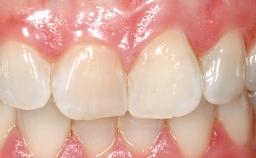

Immediate Placement of an Implant in a Maxillary Right Central Incisor Site

A 30-year-old female patient was referred to the office for the treatment of tooth 11. Her chief concern at the initial visit was to inquire, “Why is my tooth pink?” Upon clinical examination, it was determined that tooth 11 had a previous history of trauma and that the clinical crown had become noticeably pink in color as a result of internal resorption. This diagnosis was confirmed radiographically, indicating a large radiolucency involving the central and distal portions of the clinical crown. It was determined that restoration of this tooth was not possible, and that extraction was indicated. The presence of a mid-line diastema, which the patient wanted to reproduce, directed the treatment plan for tooth replacement utilizing a dental implant.